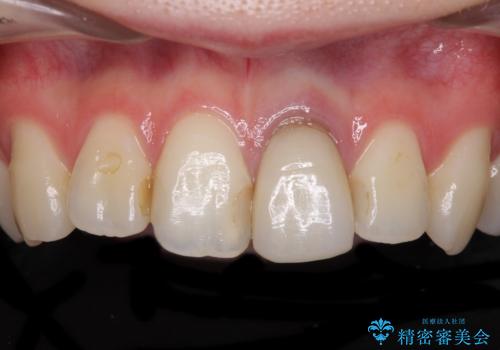

- 前歯のクラウン付近の歯肉が黒く見えることを気にして来院された患者様です。

根管治療を行った後に、オールセラミッククラウンにて補綴することとしました。